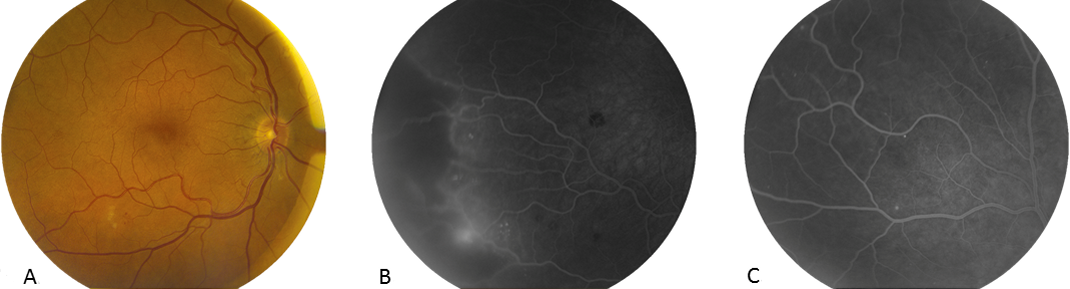

A 57-year-old man presented with a history of a rapidly progressive, bilateral, painless visual loss ongoing for two weeks. He also suffered from pain in the neck and lower back and had a weight loss of 10 kg. He underwent full ophthalmologic work-up. At presentation, BCVA was reduced to 20/40 in the right eye and 20/32 in the left eye. Slit-lamp examination was unremarkable. On fundoscopy, we noticed scattered intra-retinal haemorrhages including a few Roth spots and cotton wool lesions (Figure 1A [Fig. 1], Figure 2A,B [Fig. 2]). Fluorescein angiography revealed large areas of temporal peripheral retinal ischaemia in both eyes and neovascularisation in the right eye (Figure 1B,C [Fig. 1], Figure 2C [Fig. 2]). General history was significant for diabetes mellitus type 2 (since 15 years) and low-grade mitral valve insufficiency. The current white-centred haemorrhages together with the peripheral vascular occlusions prompted systemic investigations, primarily in search for hyperviscosity syndromes and inflammatory markers. Laboratory tests demonstrated elevated CRP of 38.8 mg/L (ref <10 mg/L) and erythrocyte sedimentation rate of 51 mm/hour (ref 4–8 mm/hour) and otherwise normal blood counts, protein electrophoresis, liver and renal function. The pain in the neck and lower back was further evaluated with bone scintigraphy revealing inflammatory hot spots scattered in both the cervical and lumbar area. An additional MRI of the spine showed both cervical and lumbar spondylodiscitis on multiple levels. This, together with raised inflammatory markers in the blood and the ocular findings guided the search towards an embolic origin. The patient underwent urgent blood cultures and ultrasonic imaging of the heart, which demonstrated mitral valve vegetations. Streptococcus mitis could be identified as causative organism for this subacute bacterial endocarditis. Treatment with ampicillin and gentamycin was started and he subsequently underwent urgent cardiac valve replacement. Unfortunately, our patient persistently refused further ophthalmologic treatment and follow-up due to general weakness and fatigue.

Figure 1: RE. A) Macula with cotton wool spots and minor microangiopathy signs temporal from the fovea; B) FFA temporal periphery highlighting an area of ischemia bordered by neovascularisation; C) FFA superior with microangiopathy